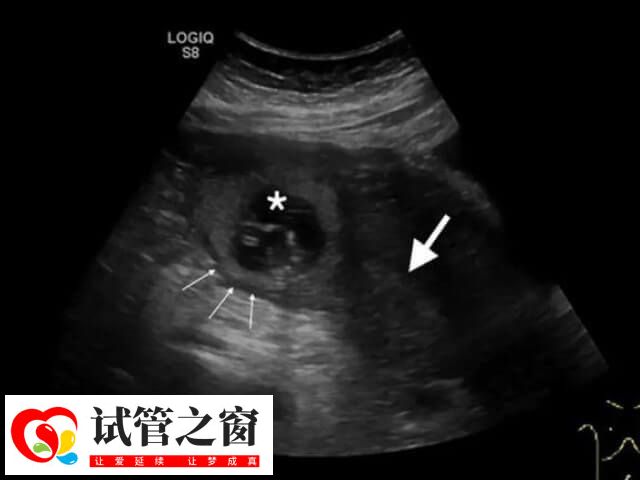

一般來說,試管移植后胚胎的最佳著床位置,是在子宮底部正中。因為這個位置的內膜厚度適中,血供和營養豐富,有利于胚胎的生長發育,但由于每個女性的宮腔內環境不同,胚胎移植后的著床位置也不同,有胚胎移植后會在子宮體前壁、后壁、側壁這些位置著床,這都是因人而異的。所以移植后的胚胎并不會一直都待在這個地方而是會在女性的宮腔內游走3-5天,尋找合適的位置著床。

醫生將胚胎移植到女性患者宮腔后,胚胎會在宮腔中處于游走狀態,在經過幾天時候后才會進行著床。而著床的位置是根據每個患者的不同宮腔環境有所差異,至于胚胎著床過程是怎樣,如下所示:

1、一般在胚胎移植后的1至2天內,它會在子宮內游走,充分的吸收營養,繼續分裂,成為1個有頭有尾的細胞分裂的囊胚;

2、在移植后的3-7天,它會長出1個小尾巴,在子宮腔內找到一個舒服的位置,如子宮體前壁、后壁、側壁這些位置,鉆進子宮壁內,從而完成著床;

3、一般在移植后的8天,胚胎就會整個陷入子宮內,由卵巢的黃體分泌HCG,在移植后的14天左右,就可以用早孕試紙檢測尿HCG,或者抽血查HCG的水平了解妊娠的情況。